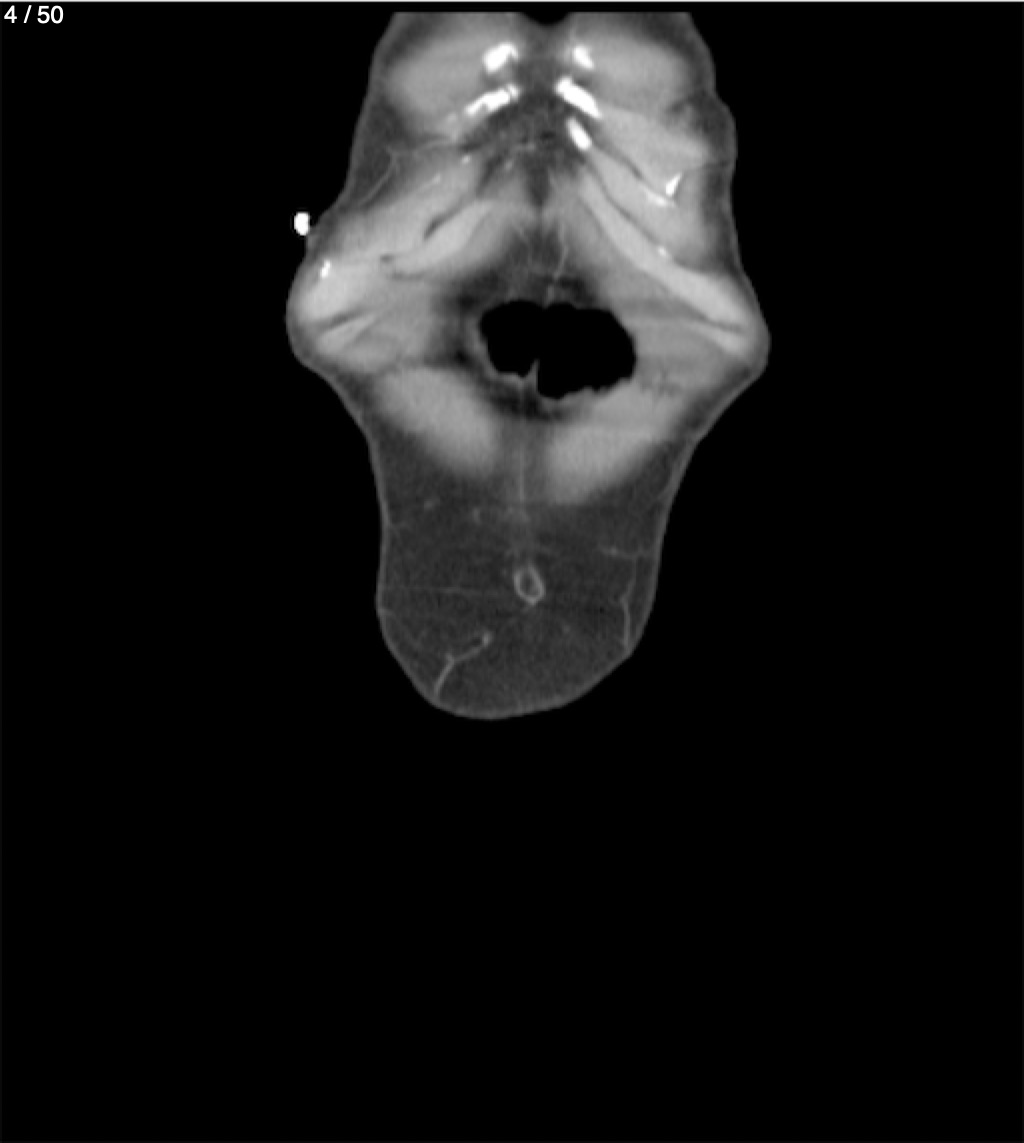

Alonso Victorio Ruiz 62A - T.C Abdomen Syc